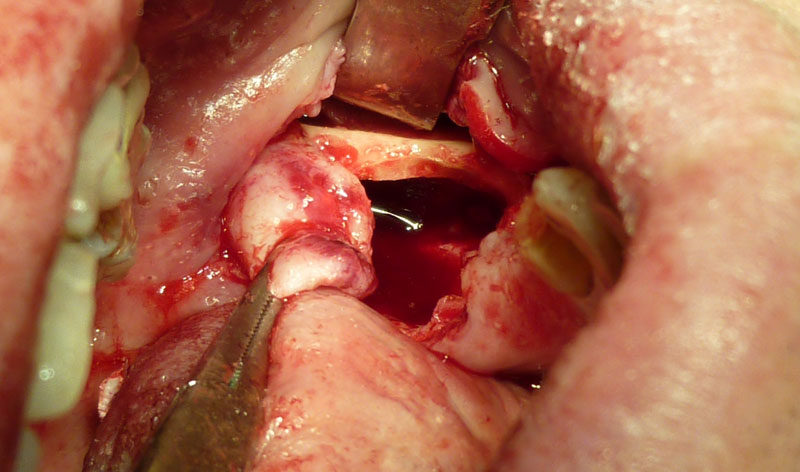

Popularmente conocido por muelas del juicio, son las intervenciones más frecuentes que se realizan. Se pueden realizar en la consulta o en los casos difíciles con sedación en hospital, siempre sin ingreso hospitalario. La duración de la intervención no suele ser superior a 10 minutos por cordal, con una recuperación entre dos y tres días.

Dada su localización anatómica, en muchos casos el cordal se haya situado junto al nervio dentario, lo que aconseja un estudio radiológico preciso para situar con exactitud la relación entre cordal y nervio dentario.